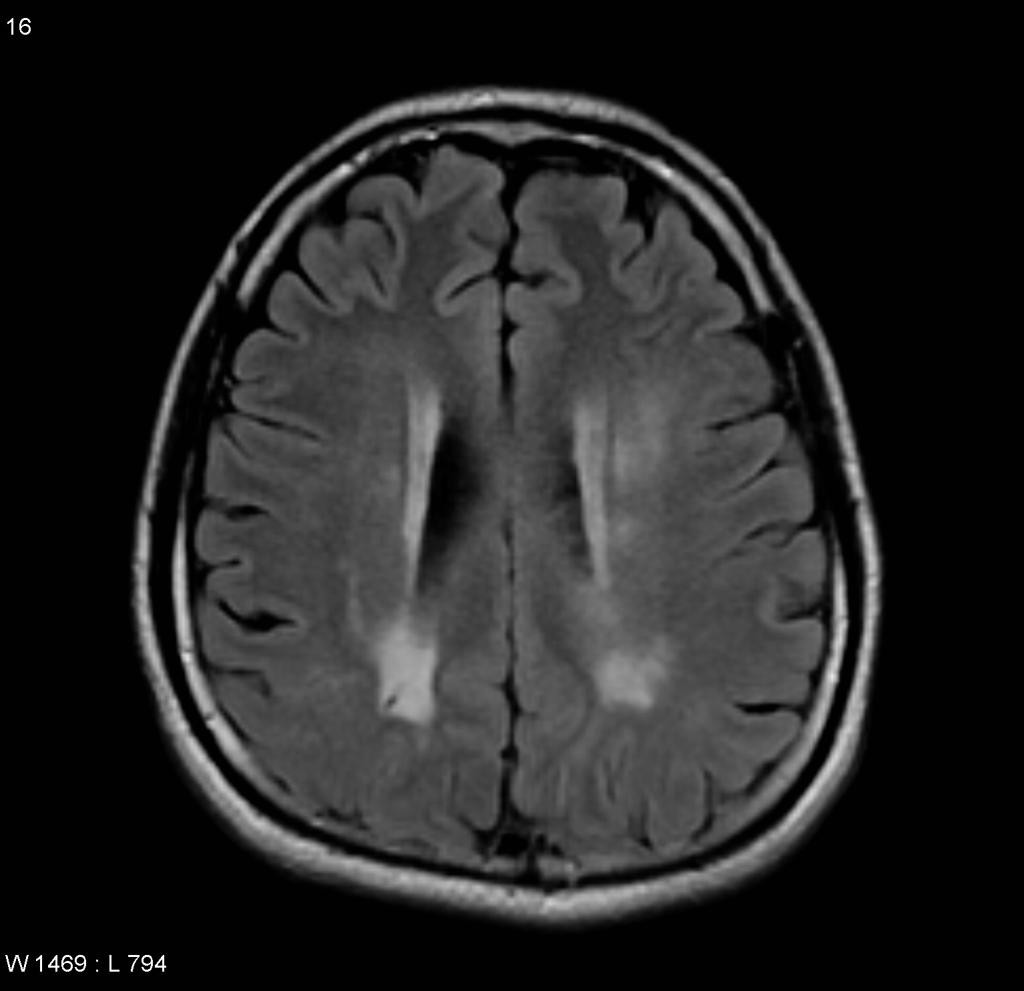

CADASIL

• Cerebral Autosomal Dominant Arteriopathy with Subcortical Infarcts and Leukoencephalopathy

• Artériopathie cérébrale autosomique dominante avec infarctus sous-corticaux et leucoencéphalopathie

• Démence vasculaire héréditaire

• Atteinte de la substance blanche des lobes temporaux et des capsules externes en plus du reste de la SB déjà atteinte dans la leucoaraiose